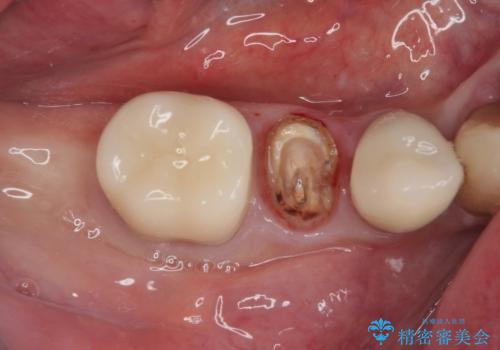

- 奥歯に装着していたクラウンが外れてしまったとのことで来院された患者様です。

診察したところ、歯根に破折線が確認され抜歯が必要な状態でした。

歯肉や歯槽骨の状態は良好であったため、抜歯即時埋入インプラントによる補綴治療を行うこととしました。

抜歯、インプラント埋入、仮歯の装着を1度に行うことができ、治療終了までわずか3か月で終えることができました。